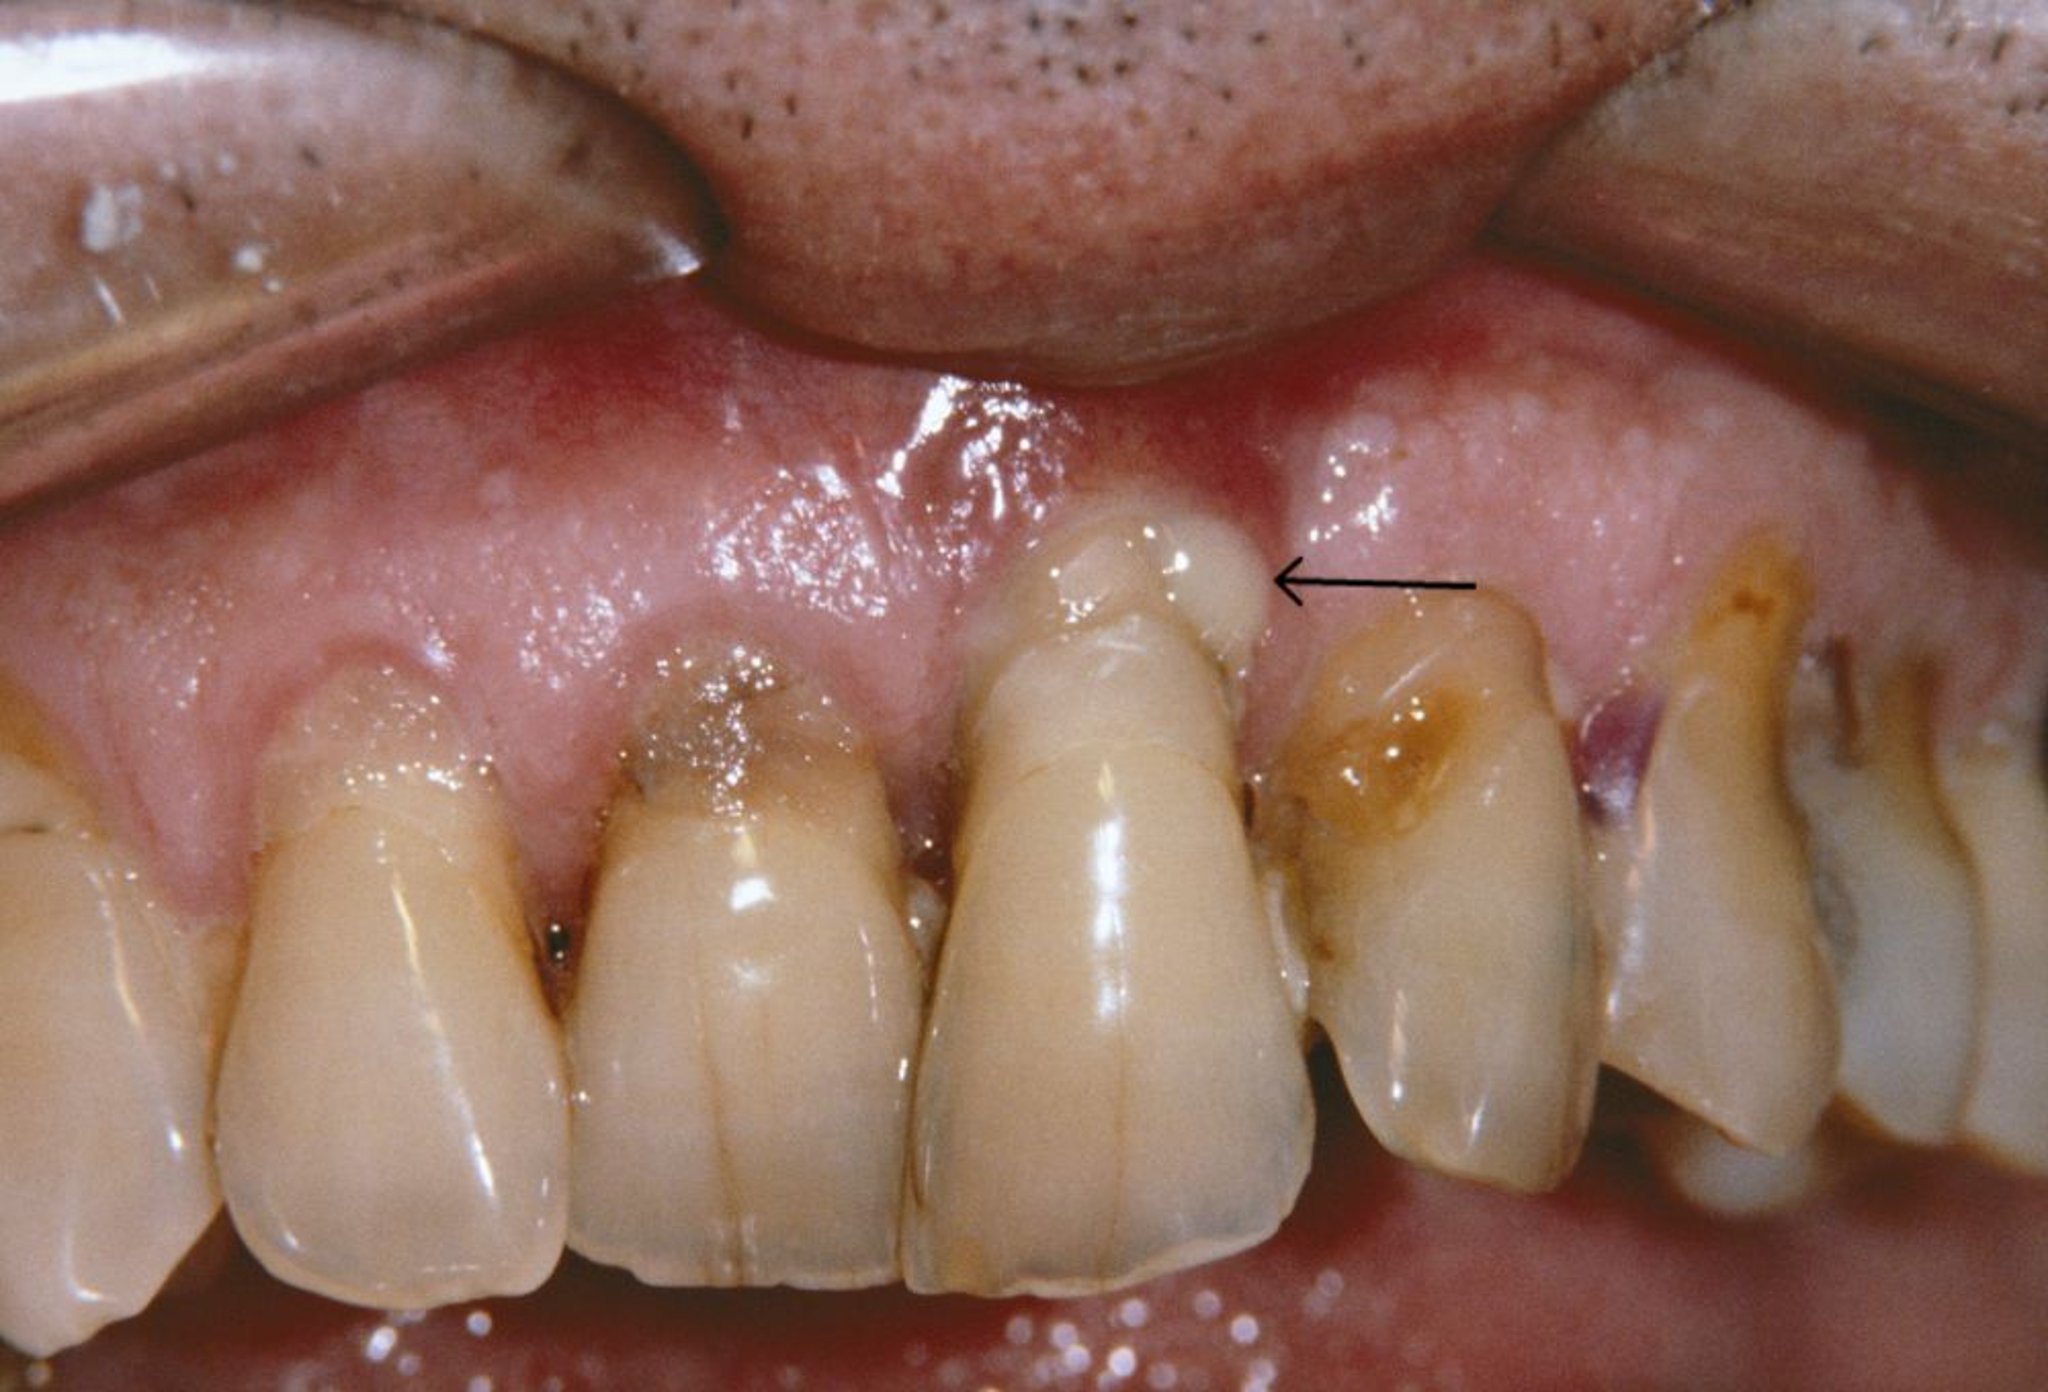

Cette photo montre des gencives rétractées et un abcès parodontal (flèche) chez une personne atteinte de parodontite.